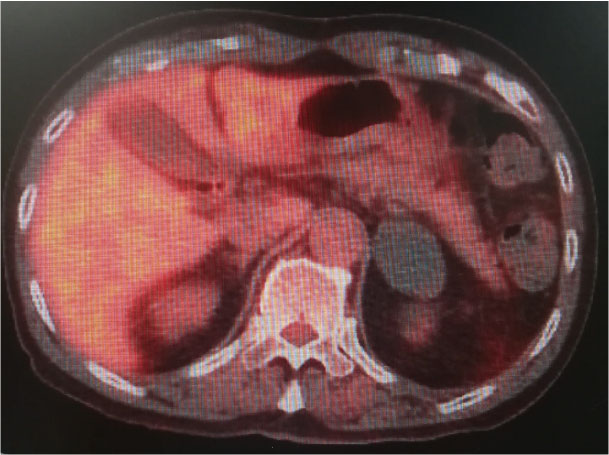

・腹部CT:46 x 36mmの左副腎腫瘤。20HU

・PET-CT:良性病変疑い